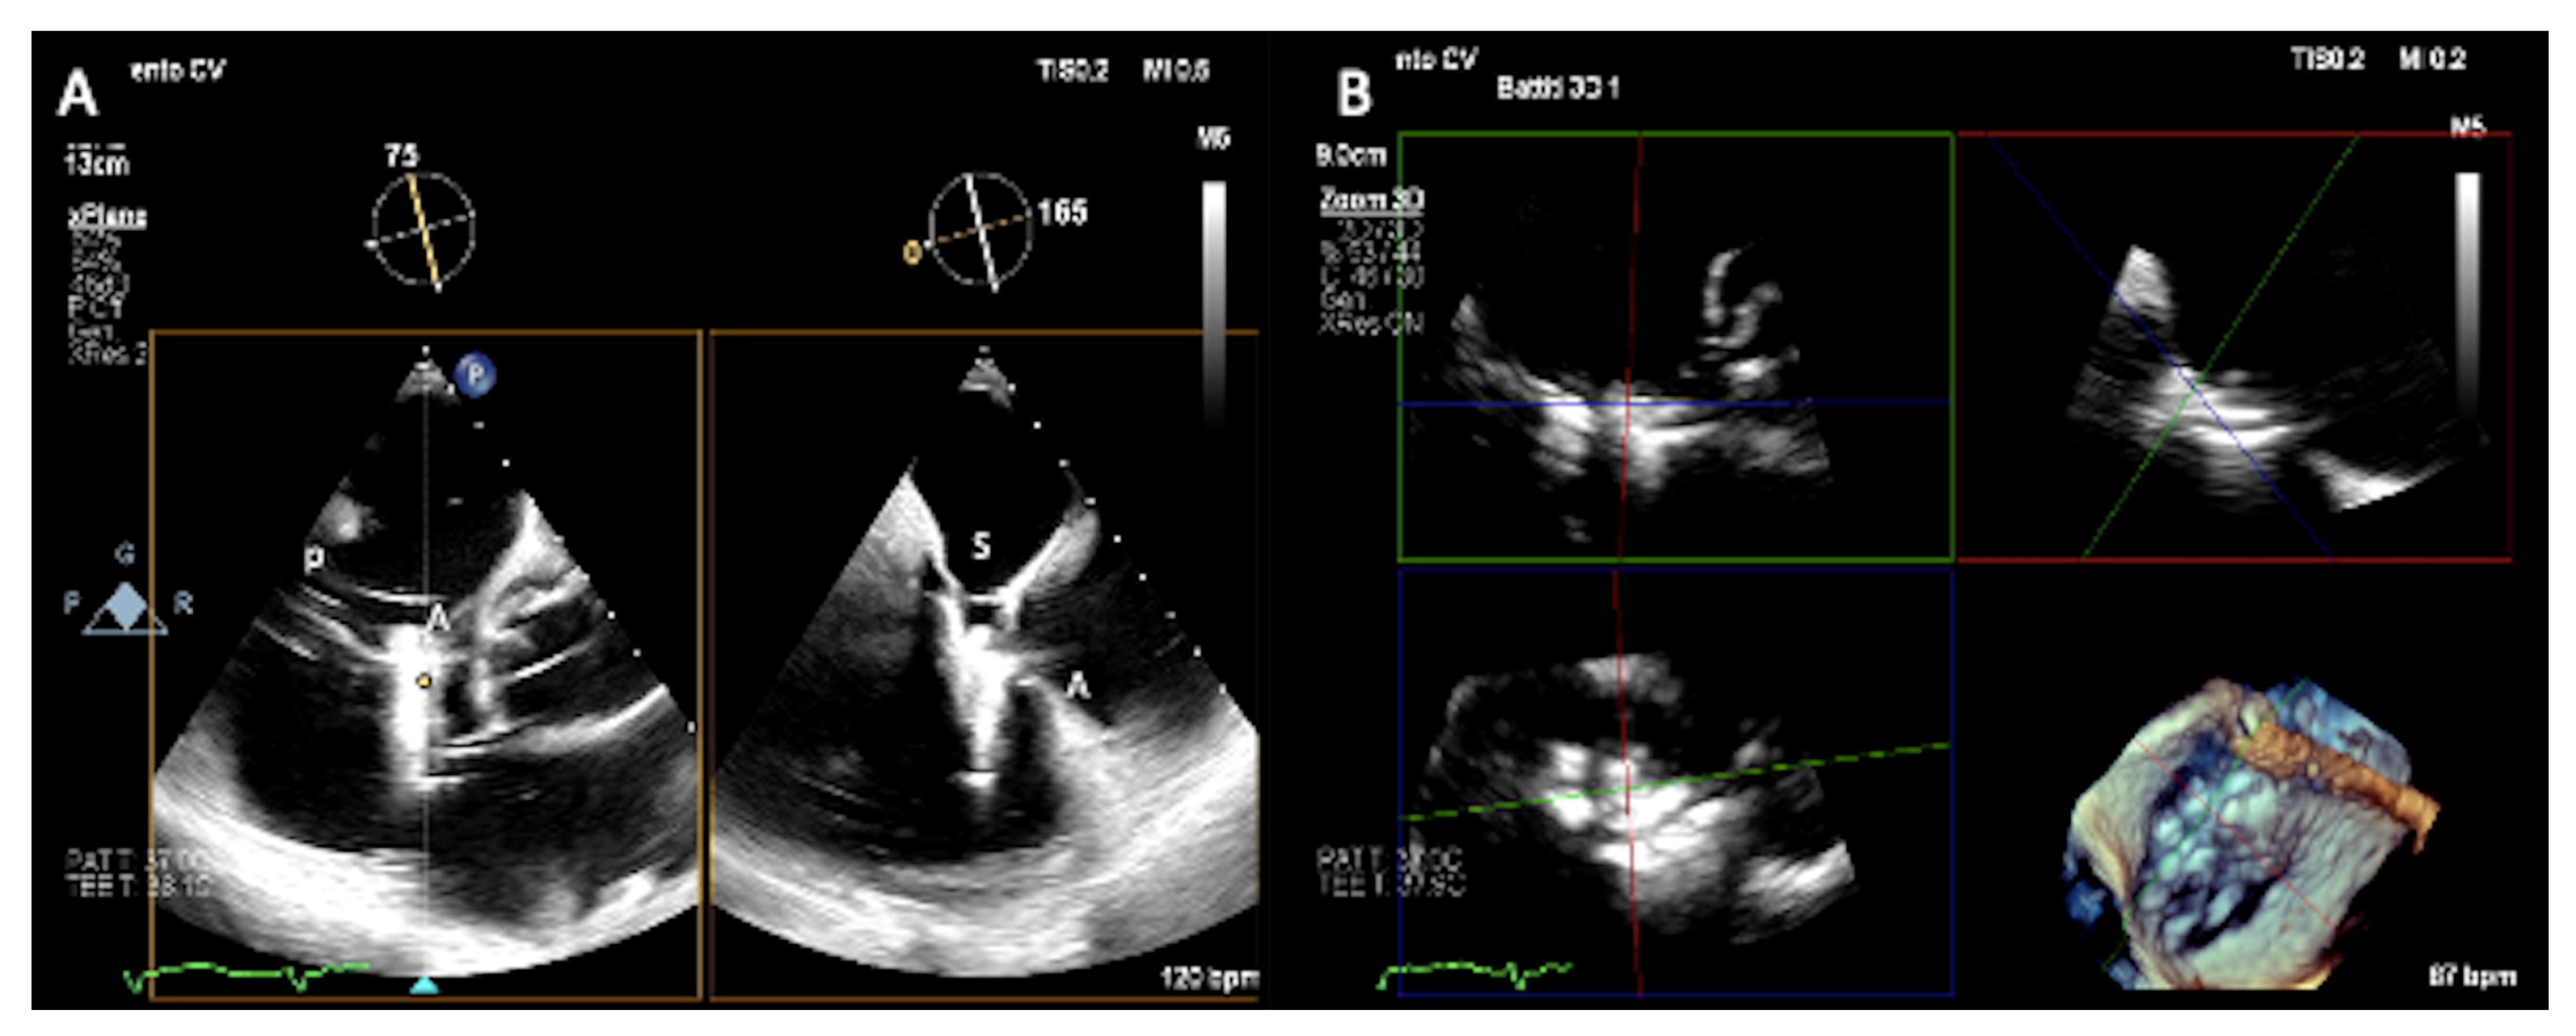

3.1. Two-Dimensional and Three-Dimensional Transesophageal Echocardiography

- Prihadi, E.A.; Delgado, V.; Hahn, R.T.; Leipsic, J.; Min, J.K.; Bax, J.J. Imaging Needs in Novel Transcatheter Tricuspid Valve Interventions. JACC Cardiovasc. Imaging 2018, 11, 736–754. [Google Scholar] [CrossRef]

- Hahn, R.T.; Saric, M.; Faletra, F.F.; Garg, R.; Gillam, L.D.; Horton, K.; Khalique, O.K.; Little, S.H.; Mackensen, G.B.; Oh, J.; et al. Recommended Standards for the Performance of Transesophageal Echocardiographic Screening for Structural Heart Intervention: From the American Society of Echocardiography. J. Am. Soc. Echocardiogr. 2021, 35, 1–76, Erratum in J. Am. Soc. Echocardiogr. 2022, 35, 447. [Google Scholar] [CrossRef] [PubMed]

- Hahn, R.T.; Kodali, S.K. State-of-the-art intra-procedural imaging for the mitral and tricuspid PASCAL Repair System. Eur. Heart J. Cardiovasc. Imaging 2022, 23, e94–e110. [Google Scholar] [CrossRef]

- Hahn, R.T.; Nabauer, M.; Zuber, M.; Nazif, T.M.; Hausleiter, J.; Taramasso, M.; Pozzoli, A.; George, I.; Kodali, S.; Bapat, V.; et al. Intraprocedural Imaging of Transcatheter Tricuspid Valve Interventions. JACC Cardiovasc. Imaging 2019, 12, 532–553. [Google Scholar] [CrossRef]

- Ro, R.; Tang, G.H.L.; Seetharam, K.; Khera, S.; Sharma, S.K.; Kini, A.S.; Lerakis, S. Echocardiographic Imaging for Transcatheter Tricuspid Edge-to-Edge Repair. J. Am. Heart Assoc. 2020, 9, e015682. [Google Scholar] [CrossRef] [PubMed]

- Ancona, F.; Stella, S.; Taramasso, M.; Marini, C.; Latib, A.; Denti, P.; Grigioni, F.; Enriquez-Sarano, M.; Alfieri, O.; Colombo, A.; et al. Multimodality imaging of the tricuspid valve with implication for percutaneous repair approaches. Heart 2017, 103, 1073–1081. [Google Scholar] [CrossRef] [PubMed]

- Agricola, E.; Ancona, F.; Stella, S.; Rosa, I.; Marini, C.; Spartera, M.; Denti, P.; Margonato, A.; Hahn, R.T.; Alfieri, O.; et al. Use of Echocardiography for Guiding Percutaneous Tricuspid Valve Procedures. JACC Cardiovasc. Imaging 2017, 10, 1194–1198. [Google Scholar] [CrossRef]